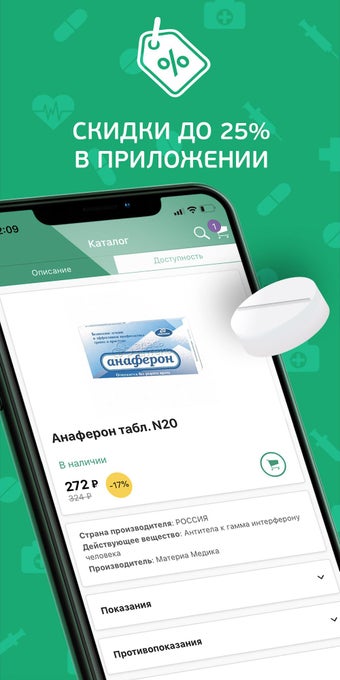

Ứng dụng cung cấp đầy đủ hướng dẫn cho mỗi loại thuốc. Bạn có thể chọn một loại thuốc dựa trên chất hoạt động của nó, hoặc sử dụng nó cho các triệu chứng. Ví dụ, nếu bạn cần một loại thuốc để điều trị huyết áp cao của mình, bạn có thể chọn một loại thuốc để điều trị tăng huyết áp. Hoặc nếu bạn bị nhiễm trùng dạ dày, bạn có thể chọn một loại thuốc để điều trị viêm dạ dày.